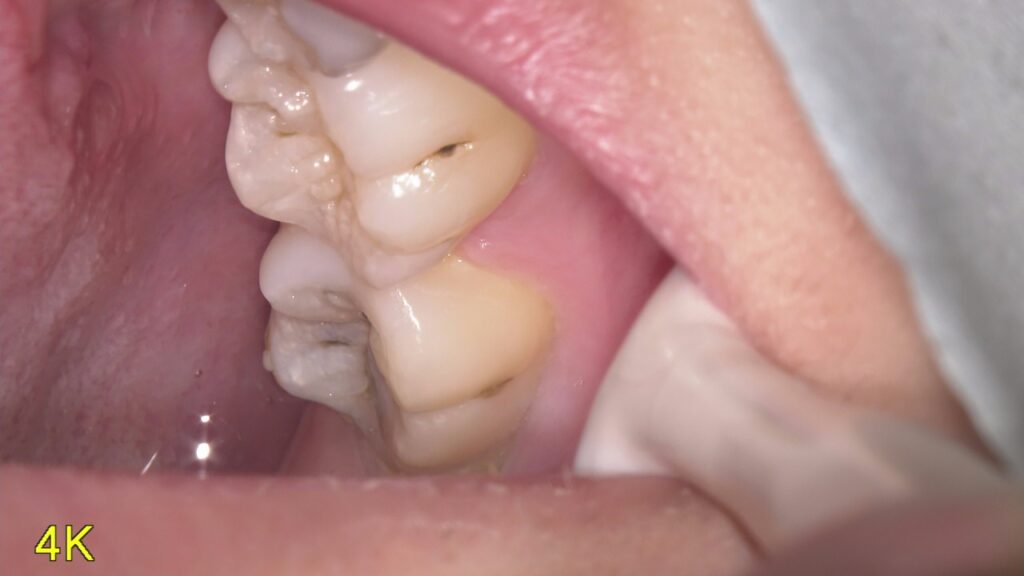

虫歯って患者さん本人には見えない位置にあったりしてなかなわかりにくいですよね

そのために当院では口腔内カメラを内蔵したマイクロスコープを使用して口腔内を説明しています。

写真を撮ったり、動画を撮ったりいろいろ使えるので重宝しています。

今回の写真は普段見えない位置の虫歯を撮影してみました。まだ小さいので症状はなにもないですが放置していたら広がってかけたり痛みが出てくると考えられるのでその前にしっかりと治していくのが大事です。

どんだけお話しするより現物を見てもらったほうがイメージわきますしどうなってるかわかるのでやはり動画や写真は大事なんだなと痛感しています。